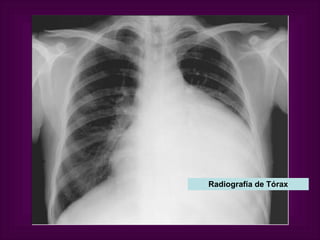

Aumento de tamaño de la silueta cardíaca  en presencia de derrame pericárdico importante  ( > 250 ml), con forma de «cantimplora».   Radiografía de Tórax

Radiografía de Tórax